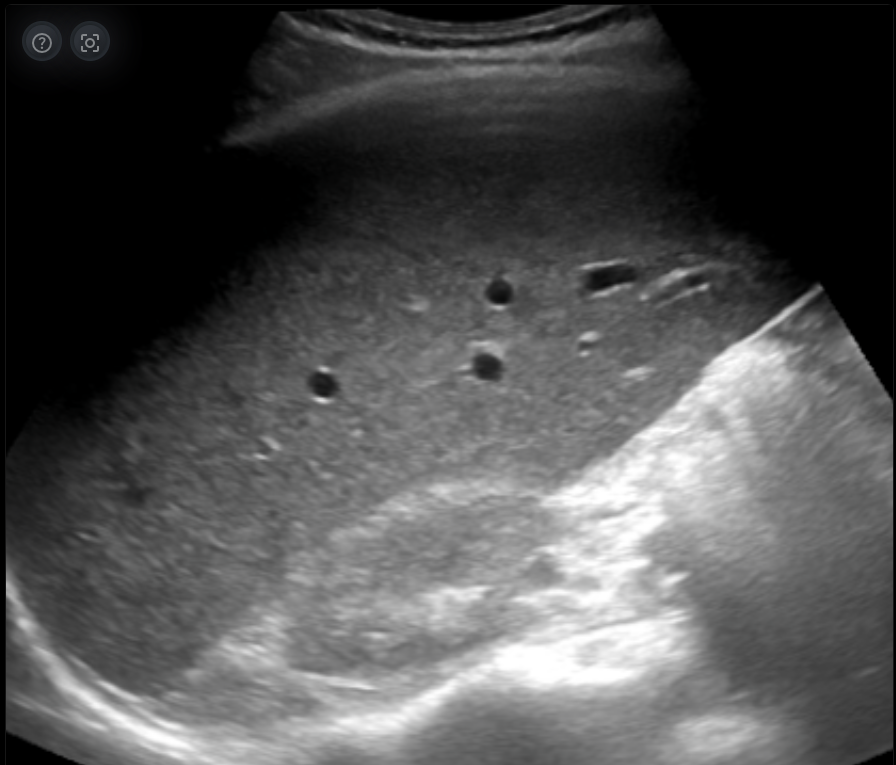

Profundidad y Penetración

La profundidad es el rango en el que el ultrasonido puede penetrar y devolver una imagen. A medida que las ondas se adentran en el cuerpo, su intensidad se atenúa. La capacidad de penetración se optimiza con frecuencias bajas, pero a costa de la resolución de la imagen. La elección de la profundidad adecuada permite al operador ajustar el rango visualizado en función de la estructura que se desea estudiar.

Explora más sobre Profundidad y Penetración en el simulador interactivo.

Profundidad y penetración en ecografía

Imagenus 3: Ejemplo de imagen de ecografía mostrando diferentes profundidades.